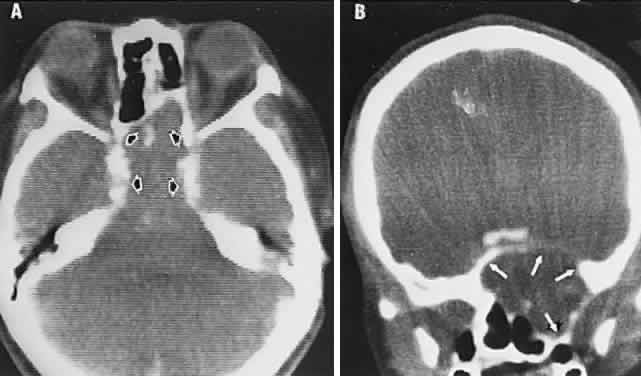

The visual field defects with arterial occlusion are variable, but they usually take the form of arcuate scotomas or “altitudinal hemianopias” of the superior or inferior half fields (Fig. 6). These altitudinal or pseudo-quadrantic defects are dense and are easily discovered by hand- or finger-counting confrontation techniques. The localizing value of the position of the “vertex” of quadrantic and wedge-shaped defects was pointed out by Alfred Kestenbaum. When the wedge originates at or points toward the blind spot, the defect is due to a retinal arterial occlusion or a lesion at the edge of the optic disc (including the arcuate defects seen in glaucoma). The differential diagnosis of arcuate scotomas, that is, with radial borders originating at the blind spot (see Fig. 6, right field), includes glaucoma, ischemic optic neuropathy, branch retinal artery occlusion, hyaline bodies of optic disc, congenital optic pit, juxtapapillary inflammation, and, rarely, chiasmal interference (see Volume 2, Chapter 6, Fig. 1F).

Fig. 6. Field defects of vascular origin. RE. Arcuate nerve fiber bundle defect of the right eye extending from the blind spot into the nasal quadrant. LE. Inferior altitudinal “hemianopia” of the left eye. These patterns are common to both retinal arterial occlusions and segmental infarction of nerve head (ischemic optic neuropathy).

The retinal variety may be admixed in a person who suffers the more conventional attacks of migraine. It is presumed that vasospasm in the retinal circulation determines transient hypoxia, perhaps somewhat similar to the visual cortical event. On rare occasions, the fundus has been examined during typical retinal migraine episodes, and arterial constriction has been described. Wolter and Burchfield106 photographically documented such an episode and demonstrated mild “retinal edema”; vessel narrowing is also evident (Fig. 8). Fortunately, permanent complications of retinal migraine are rare. These may take the form of central retinal artery occlusion or ischemic papillopathy (see Volume 2, Chapter 16); nerve fiber bundle visual field defects may be demonstrated (Fig. 9).

Fig. 9. An 18-year-old student with recurrent episodes of left retinal migraine. After a typical attack, he noted an inferior field defect. A. Fundus shows a defect in the superior arcuate nerve fiber bundle (between arrows: compare fiber layer below disc). B. Visual field defect corresponds to a retinal nerve fiber layer defect.